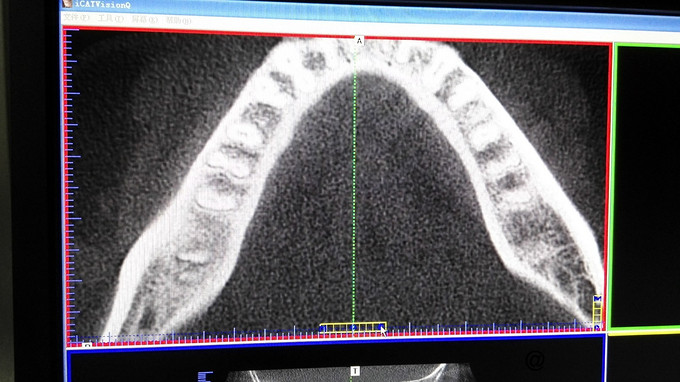

检查:右下7牙冠完整,近龈缘可见一突起脓包,少量脓血分泌物溢出,PD=10mm,余位点PD=3mm左右,叩痛(+),松动I度,电活力测试较正常牙迟钝。X线示:右下7牙槽骨水平吸收至根中,根分歧下低密度影像,远中根管增宽,可以根折。复拍CT:右下7根分歧下低密度影像,未达根尖,两根在舌侧融合,唇侧分开,唇侧无根柱,未见根折。

诊断:右下7牙周牙髓联合病变 治疗计划:右下7RCT+牙周基础治疗